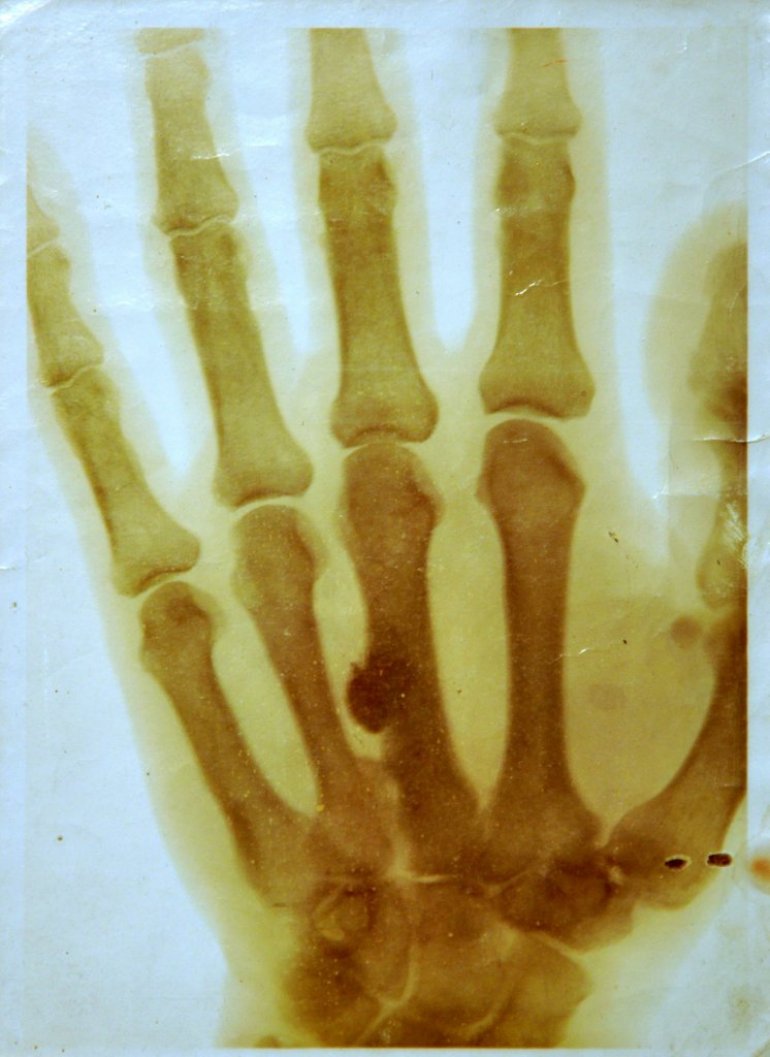

PROŠLE godine, deo izložbe Muzeja nauke i tehnike posvećene rendgen tehnologijama, bio je snimak šake kralja Petra Prvog Karađorđevića, a upravo se sada, na postavci "Vernisaž", u zdanju ovog muzeja sa Dorćola, taj neobični eksponat nalazi uz portret lekara Nikole P. Krstića (1878- 1947), koji ga je i načinio 1906. godine.

Postoji više fotografija Krstićevog rendgenskog snimka šake kralja Petra, od kojih se jedna čuva na Hiruškom odeljenju Kliničkog centra Srbije, a ova koja je izložena, prvobitno je dospela u Muzej Srpskog lekarskog društva, iz zaostavštine dr Aleksandra Kostića, našeg čuvenog histologa i seksologa, objašnjava sagovornica:

- Na snimku se vidi jedan projektil u trećoj kosti zapešća, koji je kralj Petar nosio u ruci od Francusko-pruskog rata, iz 1870, u kome je pretedent na srpski presto učestvovao kao pripadnik Legije stranaca, na strani Francuza. Koliko se zna, taj projektil nikada nije hiruški izvađen. Zanimljivo je da se sa pruske strane borio akademik Vladan Đorđević, osnivač Srpskog lekarskog društva i Društva Crvenog krsta, koji je bio isto godište i išao je u istu beogradsku gimnaziju.